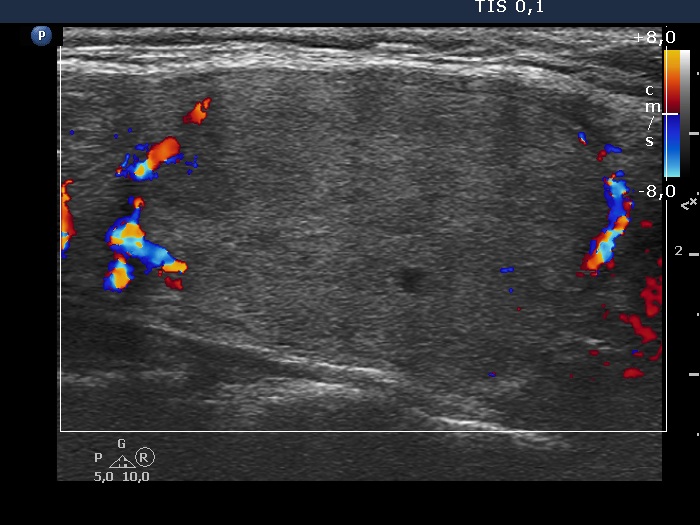

Follicular carcinoma - Case 2. (ultrasound picture 6)

Left lobe, longitudinal scan, color Doppler mode.